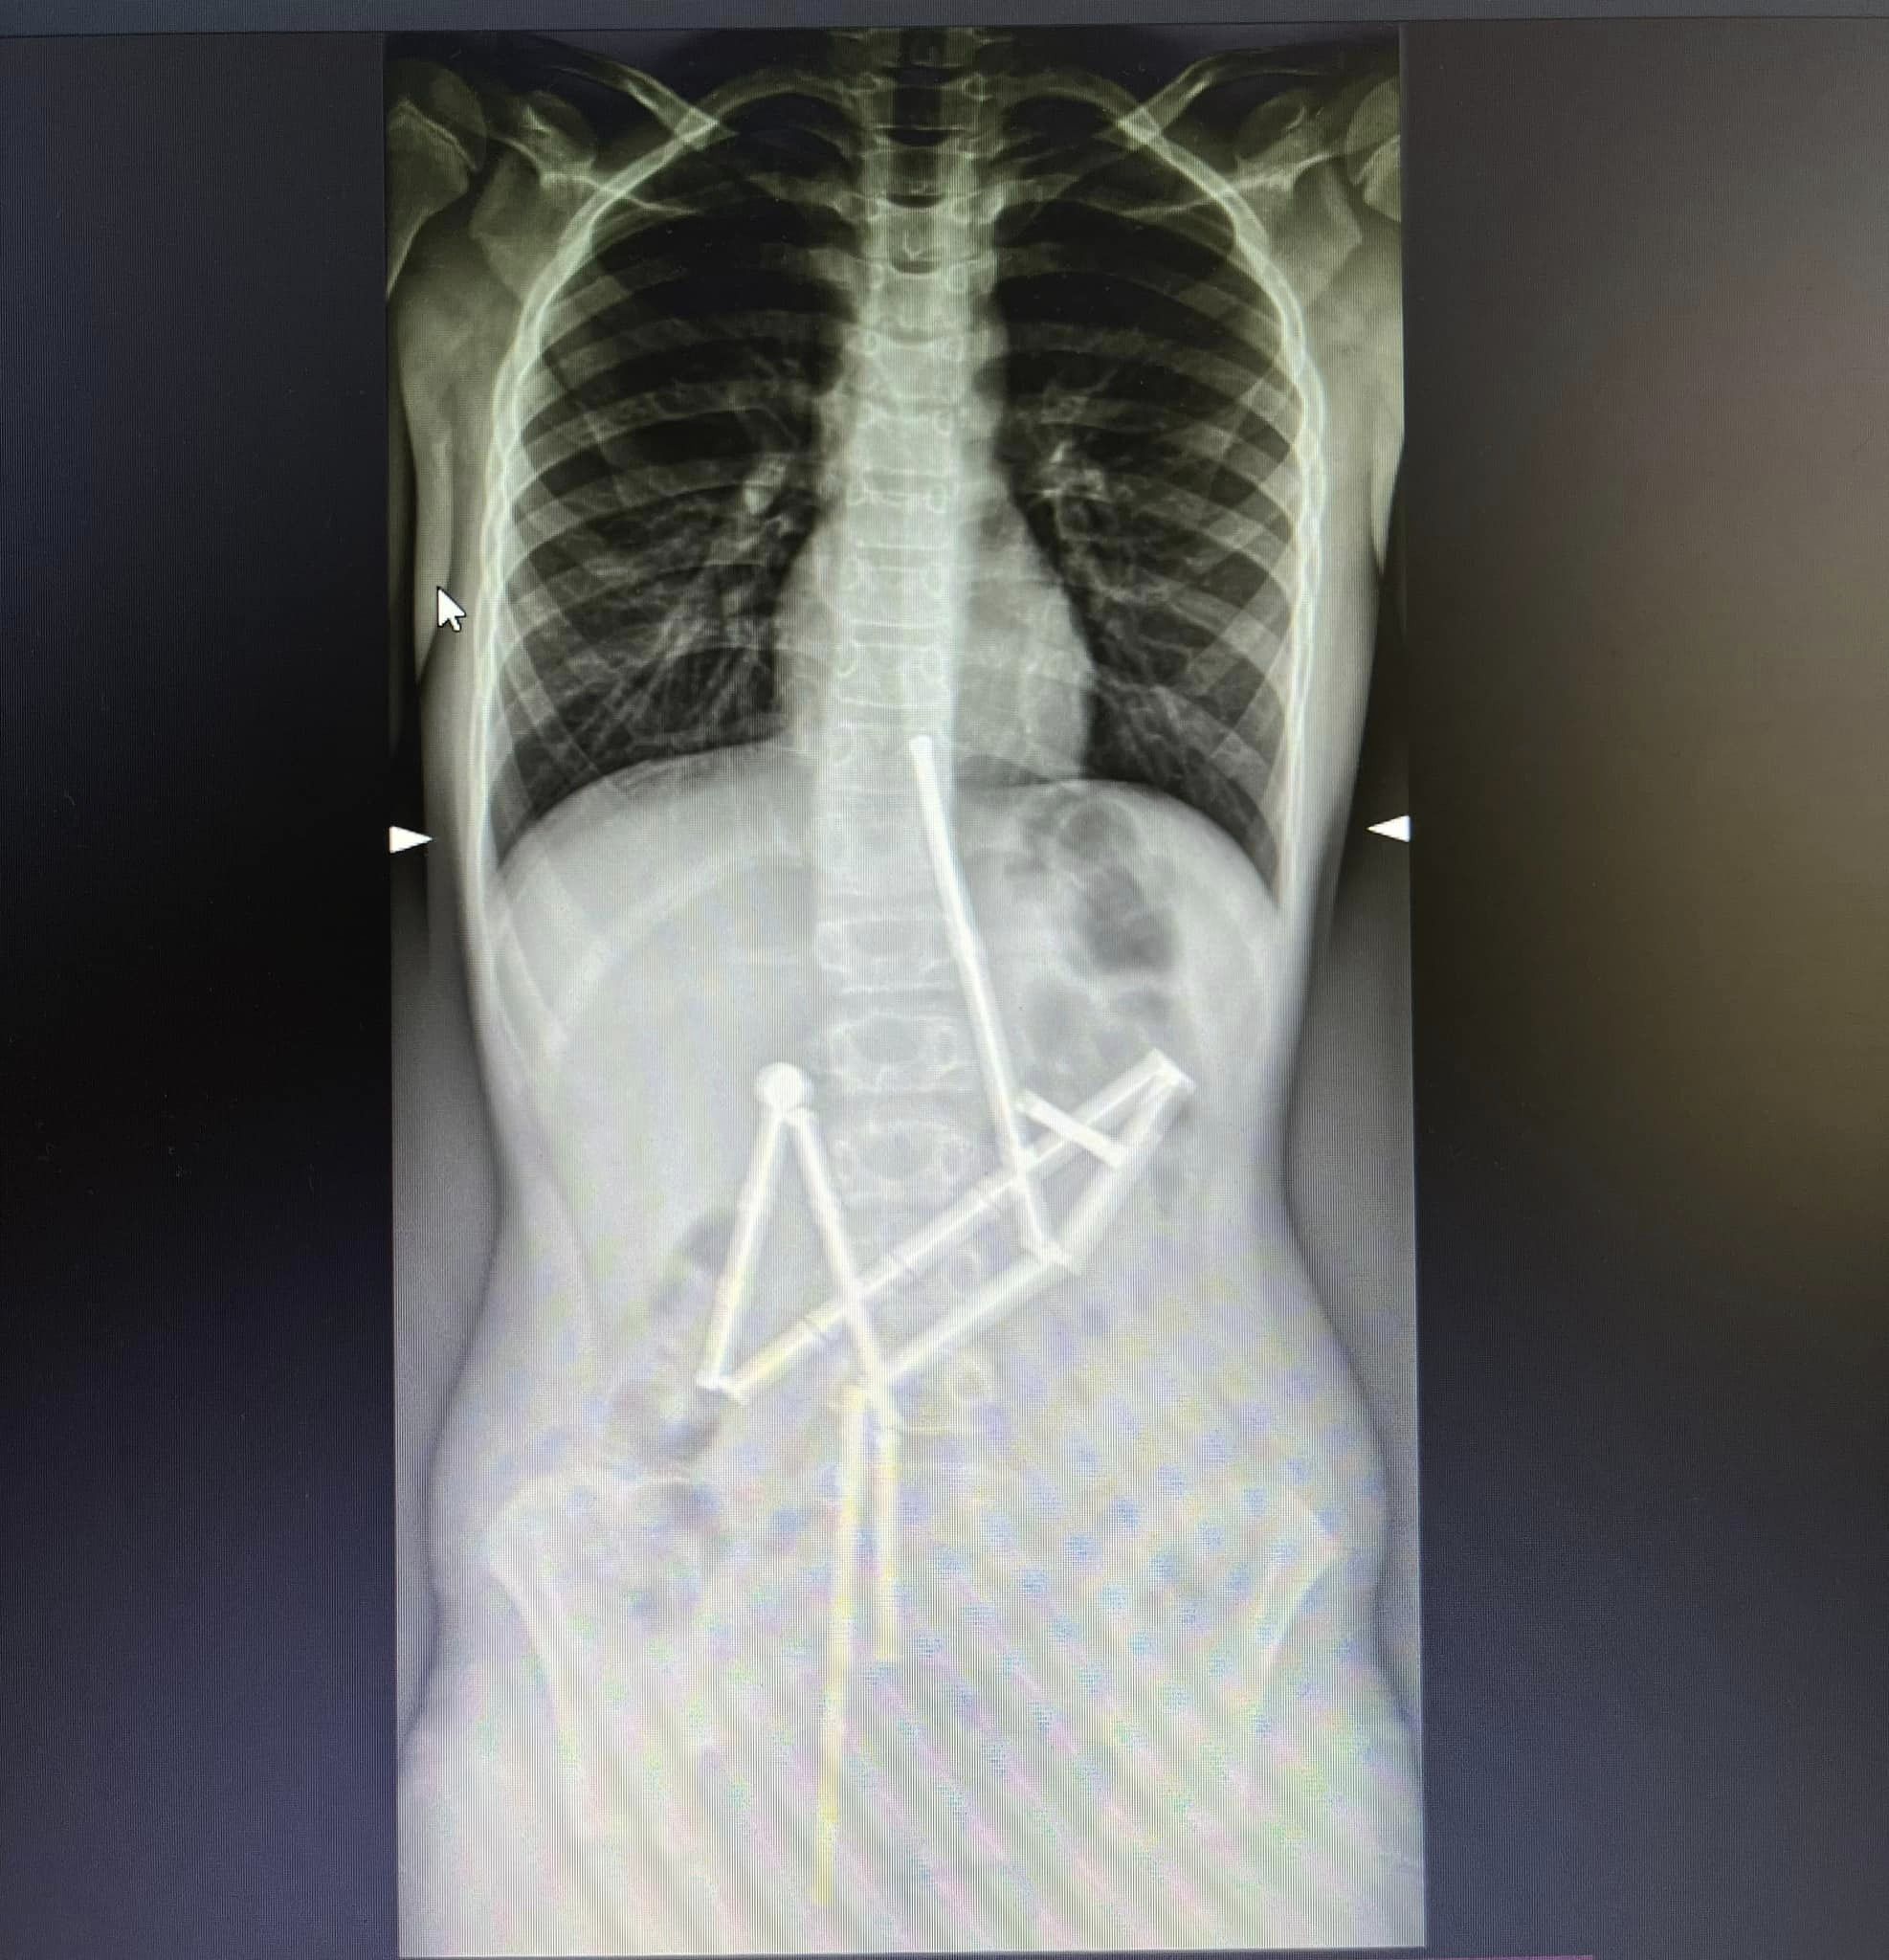

"<...> Уже на первом рентген-снимке специалисты увидели наличие в пищеварительном канале целой группы инородных тел, в которых удалось узнать магнитный конструктор. 20 магнитов находились в разных частях желудочно-кишечного тракта, и были соединены между собой. Консилиумом врачей было принято решение о проведении неотложного оперативного вмешательства", - сообщают в клинике.

Рентгеновский снимок. Истоник - facebook.com/ndslohmatdyt